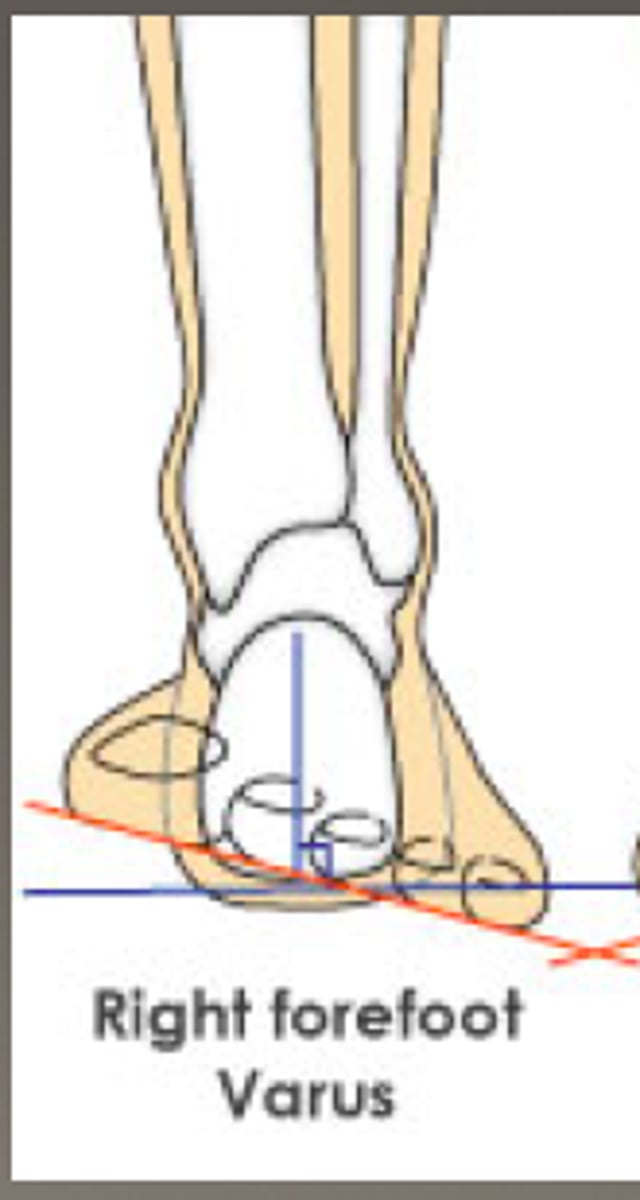

forefoot varus

- inversion of forefoot

- subtalar joint in neutral

forefoot valgus

- eversion of forefoot